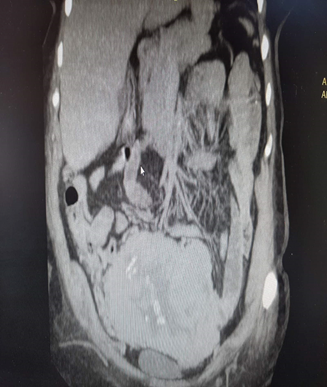

Figure 3 CT depiction of pelvic solitary fibrous tumor.

Figure 4 CT depiction of pelvic solitary fibrous tumor.

Figure 5 CT depiction of pelvic solitary fibrous tumor.

Abdominal CT revealed presence of enormous solid lesion with small lobular posterior line, which also bears cystic elements, necrosis and calcifications in its interior.

Formation diameter among 15,3X14,1X14,8 cm, obfuscating extended segments of descent colon and recto sigmoid which are in incomplete development, coming in contact with the uterus and bilateral adnexa, obfuscating them as well.

It also exerts pressure on the urinary tract. Other formations free of malignancy. Thorax CT did not reveal any pathological formations. Resuming all appropriate imaging findings, optimal therapeutic strategy reflected surgical dissection of the lesion and optimal staging. Due to size tumor, suprahypocephalic section entering the peritoneal cavity was performed.